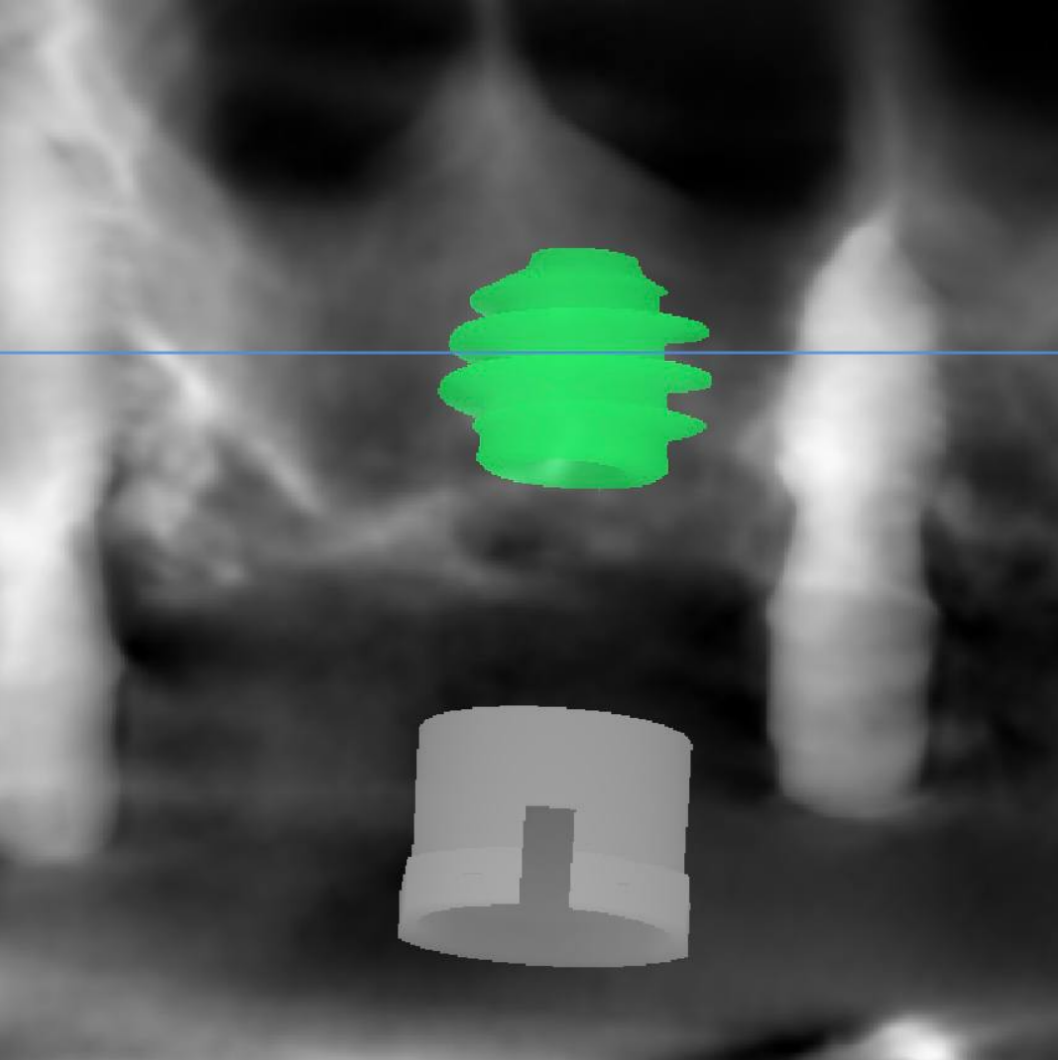

Закрытый синус-лифтинг в области перегородки. Время операции сокращено до 15 минут, вместо стандартного протокола. Значительно меньшее время до нагрузки импланта, чем при открытом синус-лифтинге.

Для данного кейса выбран имплантат AnyRidge 7,5 x 7,0 мм. Торк при внедрении был 16 Н/см, но ISQ = 50 ед.!

Виртуальное планирование и хирургический шаблон в данном случае – не просто удобный инструментарий, а критически важные аспекты для:

• Безопасности (уменьшить риск перфорации мембраны)

• Скорости (операция проходит значительно быстрее)

• Комфорта пациента (сокращается восстановительный период)